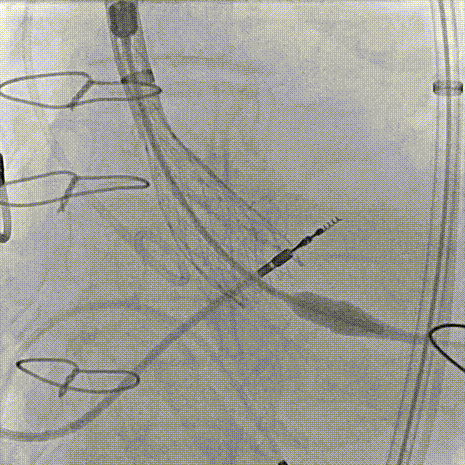

80%工作位评估